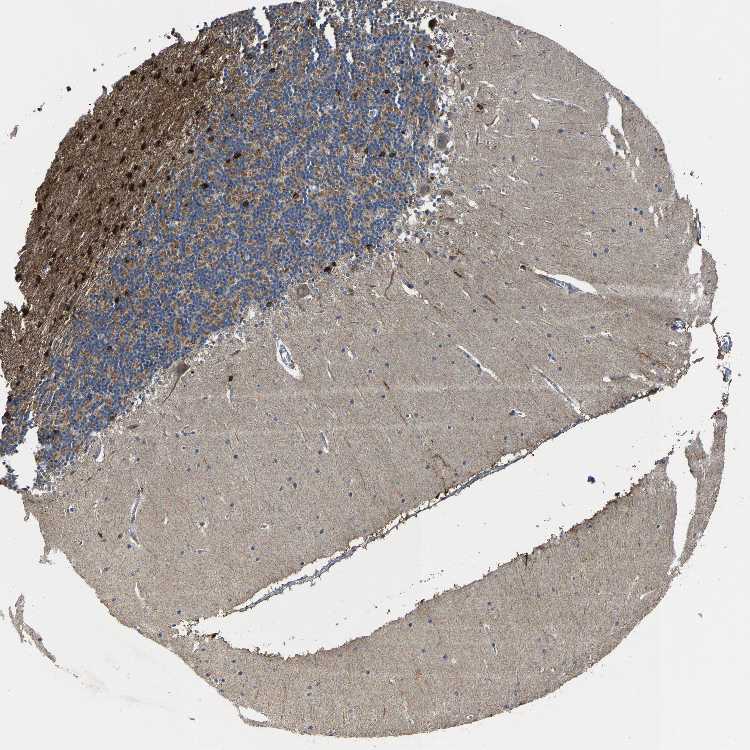

CEREBELLUM - Antibody stainingi

Antibody staining in the annotated cell types in the current human tissue is reported as not detected, low, medium, or high, based on conventional immunohistochemistry profiling in selected tissues. This score is based on the combination of the staining intensity and fraction of stained cells.

Each image is clickable and will lead to virtual microscopy that enables deeper exploration of all samples and also displays staining intensity scores, fraction scores and subcellular localization as well as patient and tissue information for each sample.

Antibody HPA020959Antibody HPA053471

Purkinje cells Not detectedMedium

Cells in granular layer MediumMedium

Cells in molecular layer MediumLow